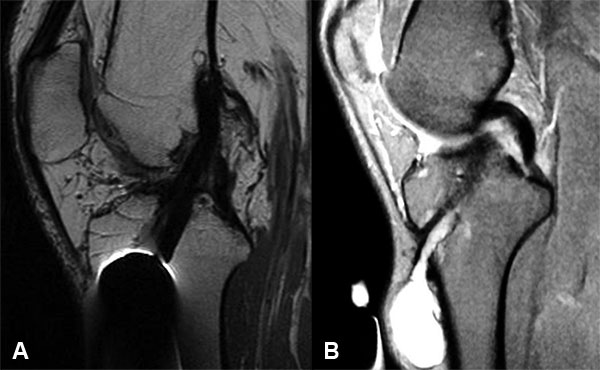

Se evaluaron 14 pacientes, nueve masculinos y 5 femeninos, con una edad promedio de 38 años (rango entre 26 y 55 años). El seguimiento promedio fue de 35 meses (rango entre 6 y 94 meses). El tiempo promedio entre la cirugía primaria de LCA y la aparición del quiste fue de 29 meses (rango entre 13 y 48 meses) (Tabla 1). Clínicamente todos cursaron con dolor anterior de rodilla a nivel del túnel tibial, con una tumoración palpable. En ningún caso se evidenciaba eritema ni signos de infección, con resultados de laboratorio negativos. Ninguno presentaba maniobras de Lachmann o Pivot Shift positivos, ni sensación subjetiva de inestabilidad. Todas las RM mostraron un neo-ligamento continuo en todos los pacientes (fig. 1a) y el tamaño de los quistes varió entre 1.1 cm a 3 cm (fig. 1b). Si bien todos presentaban características benignas, en todos los pacientes se podía apreciar un aumento del diámetro del túnel tibial con una interfase lineal hiperintensa en T2 correspondiente a líquido alrededor del injerto entre el quiste y la articulación.

Figura 1: A) Neoligamento continuo. B) Quiste 2.5 cm.